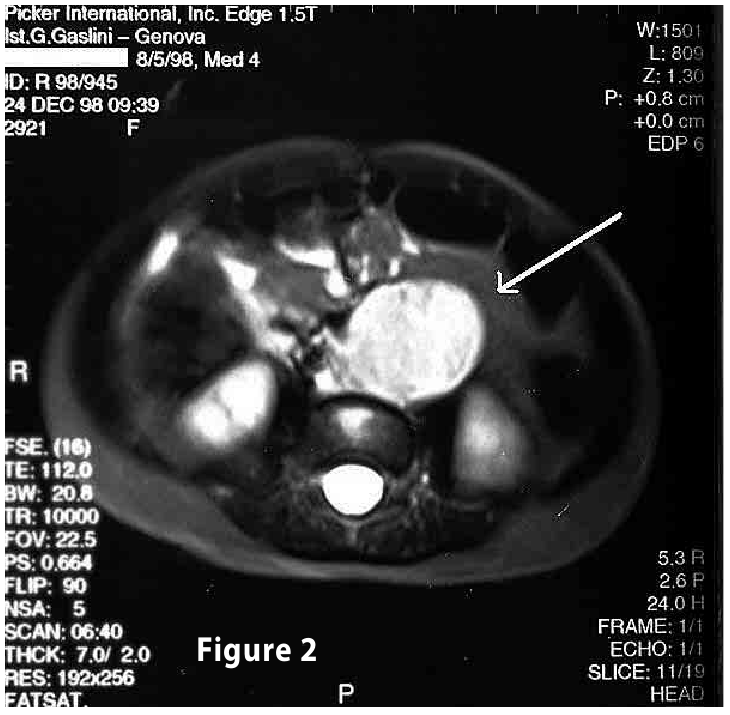

Complete objective response of neuroblastoma to biological treatment.

Figure2